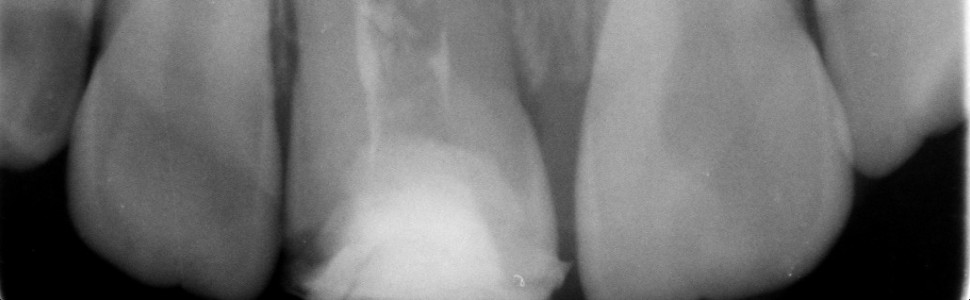

Leczenie endodontyczne zębów stałych niedojrzałych różni się od standardowego leczenia zębów z zakończonym rozwojem. Potrzeba leczenia endodontycznego młodych zębów często wynika z powikłań urazów zębowych u dzieci. Opis przypadków: W pracy opisano dwa przypadki pacjentów w wieku rozwojowym po urazie zębów stałych przednich, którzy zostali skierowani do Zakładu Stomatologii Wieku Rozwojowego (ZSWR) w Łodzi celem pogłębienia diagnostyki żywotności miazgi przy użyciu laserowego Dopplera Laser Doppler Flowmetry (PeriFlux, Szwecja). U pacjentki L.J., lat 6, doszło do złamania korony zęba 11 – rozwój korzenia tego zęba był na wczesnym etapie („F” wg Demirijana). Przez kolejne 2 lata obserwowano zamykanie się wierzchołków korzeni zębów siecznych, wykonywano też badania przepływu naczyniowego miazgi – LDF. Jednak po 2 latach, już po zakończeniu się rozwoju korzenia, u pacjentki wystąpiły objawy bólowe zęba 11. Stwierdzono obumarcie miazgi i wykonano standardowe leczenie endodontyczne. U pacjenta F.M., lat 10, doszło do złamania korony zęba 11 z obnażeniem miazgi. Stwierdzono niezakończony rozwój korzenia (faza przedostatnia „G” wg Demirijana). U pacjenta wykonano amputację częściową miazgi. Początkowo ząb reagował na bodźce zimna, ale przepływ naczyniowy miazgi był obniżony, a po 9 miesiącach wystąpiły objawy bólowe. Po usunięciu martwej miazgi część wierzchołkową kanału wypełniono MTA, a część środkową i koronową płynną gutaperką(Gutta Flow, Roeko). Wnioski: Stan miazgi zębów po urazie u pacjentów w wieku rozwojowym wymaga długotrwałej obserwacji. Wybór metody leczenia jest uzależniony od indywidualnego stanu klinicznego zęba oraz wieku pacjenta.